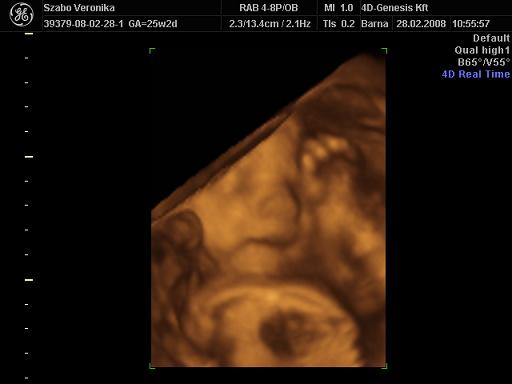

[quote="mpatr"][ írta:mpatrb]Nici, a felvétel élessége és sikerültsége sok mindentől függ.

A profi gépen túl a profi és türelmes szonográfus, a lepény és baba helyzete (mellső fali lepénynél kicsit nehezebb az ügy, meg a babák is imádnak belebújkálni a lepénybe), a magzatvíz mennyisége, a mama hasfalának zsírrétege (mennyire dagi anyuci) szóval ezek (biztos van még) min-mind befolyásolják a felvétel minőségét.

Nekem sikerült ugyanarról a gyerkőcről aki a pocimban van nagyon tuti és nagyon sz..r képet is készíteni ugyanazzal a géppel.

Érdemes többször próbálkozni.